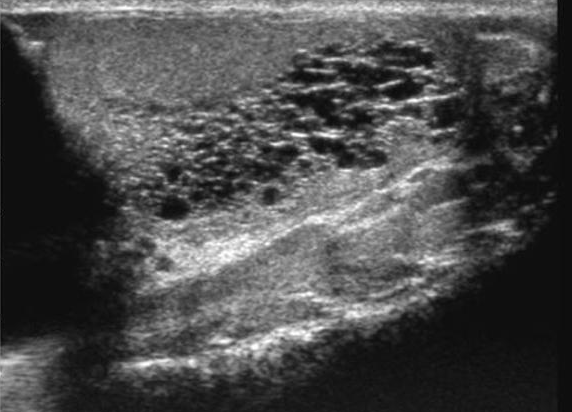

Torsion

• Look for lack of flow

• Look for lack of attachment to scrotal wall, likely suspended in a hydrocele

• Partial Torsion

• May have some blood flow

• Decreased or reversal of flow in diastole (no line in between peaks) - indicates high resistance state (top images)

• Blunted arterial peak (not as sharp as a point in systole) ( bottom images)